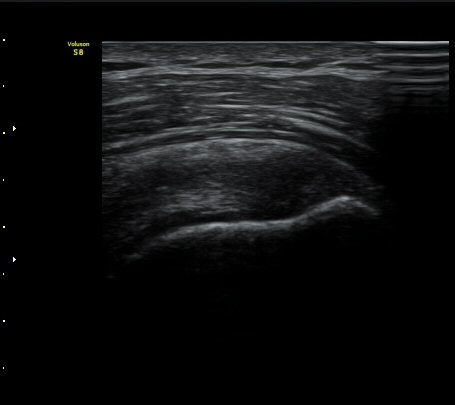

ÃÊÀ½ÆÄ °Ë»ç

±Ø»ó°Ç Á¾´Ü¸é°Ë»ç½Ã ±Ø»ó°Ç ºÎÂøºÎ¿¡ Àú¿¡ÄÚ ºÎÁ¾°ú ¹Ì¼¼ÇÑ °Ç ¿¬°á¼º ¼Ò½ÇÀÌ

°üÂûµÊ (±×¸² 1, 2, 3 )